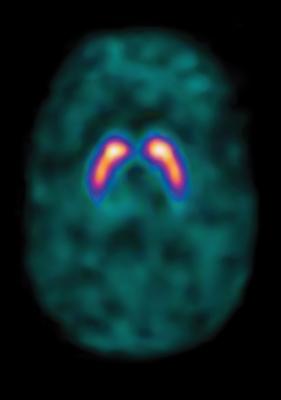

According to the Society of Nuclear Medicine and Molecular Imaging (SNMMI), more than 20 million Americans benefit each year from nuclear medicine procedures.1 Diagnostic RPs are drugs necessary for all nuclear medicine imaging studies to diagnose and determine the severity of disease. Nuclear medicine imaging procedures are effectively used in the diagnosis and treatment of disease states such as cardiovascular disease, some forms of cancer, Parkinson’s Disease, thyroid disease and epilepsy.

Diagnostic and therapeutic RPs are statutorily considered drugs and are regulated as drugs by the Food and Drug Administration. However, since 2009 diagnostic RPs under the OPPS have been packaged with the procedure into Ambulatory Payment Classifications (APCs) for a bundled payment to hospitals while therapeutic RPs continue to be paid separately. Diagnostic RP costs may vary widely within a nuclear medicine APC with some diagnostic RP costs significantly exceeding the APC payment rate.